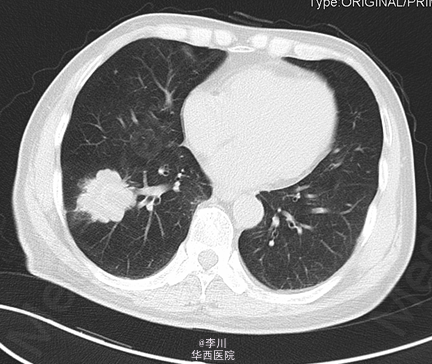

患者男,73岁,因“咳痰伴痰中带血2+月”入院。患者于2+月前无明显诱因出现咳痰伴痰中带血,无咳嗽、胸闷、胸痛等症状,未予以处理。10+天前于外院就诊,行胸部CT、心脏超声、纤支镜等检查示:右肺占位。予以口服及输液治疗13天(具体不详),症状无明显好转。

于全麻下行“VATS右肺下叶切除术+淋巴结清扫术”,术中见:肿块块位于右肺下叶,约4.2*3.9cm大小,脏层胸膜皱缩、无侵犯壁层胸膜;术中冰冻结果:(右下肺肿块)腺癌。

肺癌的分叶征是周围型小肺癌最常见的基本征象。其病理基础一是与肿瘤边缘各部位肿瘤细胞分化程度不一,生长速度不同有关;二是肺的结缔组织间隔,进入肿瘤的血管、支气管分支、从肿瘤内向外生长的血管和结缔组织等引起肿瘤生长受限并产生凹陷,从而形成分叶的形态。分叶征对于鉴别肺部包块良恶性具有重要价值。